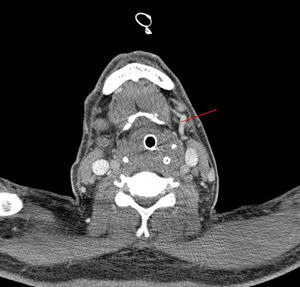

El paciente requiere durante las primeras horas amplia expansión de volemia, apoyo inotrópico, intubación orotraqueal y soporte respiratorio con ventilación mecánica. Tras la estabilización del paciente, nuevos controles radiológicos de cuello confirman la presencia de flemón en fosa amigdalar derecha que se extiende al espacio retofaríngeo, hipofaringe y espacios parafaringeo y masticador. Una TAC a la semana de evolución, muestra trombosis de la vena yugular externa derecha, en la región submandibular (fig. 1), siendo ambas venas yugulares internas permeables.